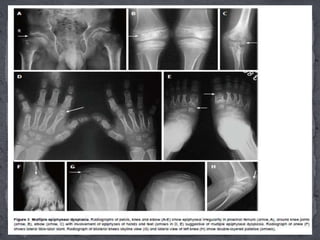

 Multiple epiphyseal dysplasia (EDM) is a genetically

heterogeneous entity caused by mutations in multiple

genes.

 Most cases of EDM are inherited in autosomal

dominant manner while EDM4 has autosomal

recessive inheritance.

 Age of manifestation: Despite the genetic

heterogeneity, MED usually presents after the age of 2-

4 years when the child begins to walk.

Essential radiographic features:

(1) Bilateral and symmetric involvement of epiphyses of hips, knees,

ankles, shoulders, elbows, wrists and hands and feet.

(2) Lateral tibio-talar slant wherein the lateral part of distal tibial

epiphyses is thinner than the medial and the trochlea of the talus is

shaped to conform to the abnormal ankle joint mortice

(3) Double-layered patella as seen on a lateral X-ray of knee is considered

highly pathognomic of EDM. However, more recently, the uncommon

occurrence of a double-layered patella is also seen in a patient with

pseudoachondroplasia.

(4) Mild involvement of spine with anterior wedging, mild end plate

irregularity and multiple Schmorl’s nodes mimicking Scheuermann’s

disease and typical absence of platyspondyly.